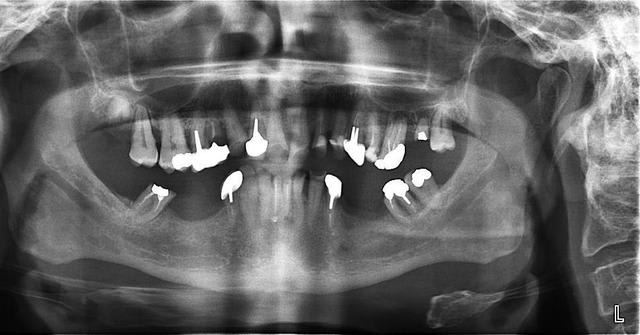

bon, difficile d'évaluer à distance...au vue de la pano et de tes photos...voilà ce que je ferais...:

-extrac de 14 et 27

-après les dévit qui s'imposent (même avec la pulpe dans les chaussettes)bridge sup en 2 parties, de 11 à 16 (que tu peux garder vivante) et 21 à 26

-Bridges inf en 3 parties, 33 à 37, 32 à 42, 43 à 47

J'ai fait une RA de 22, elle est très courte et cariée assez sous gingivale. Pas sûr du tout de la conserver.

Suis pas très chaud pour garder la 12 (LPA sous richmond)

Il y a une péche sous 26. Faut qu'on soit sûr de la garder avant de se lancer dans un bridge.

J'ai pensé aussi comme toi au bridge 32-42 mais la forme de la racine de 32 n'est pas idéale.

Le constat est le suivant, corrigez-moi si je me trompe:

on a eu des extractions non compensées à la mandibule qui ont provoquées des égressions des dents maxillaires postérieures.

une abrasion +++ du bloc antérieure avec égression "physiologique" au fur et à mesure de l'usure.

On a ainsi un décalage important (comme une marche d'escalier) de la courbe d'occlusion (Spee) entre le secteur antérieur et postérieur.

La difficulté de la thérapeutique consistera à rattraper le mieux possible ce décalage pour avoir une courbe d'occlusion "harmonieuse".